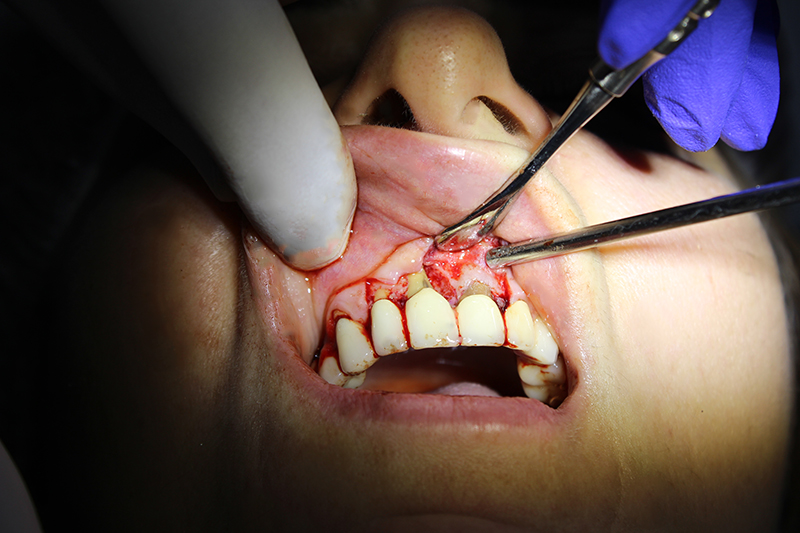

В медиальной области 11-го зуба пациентки была резорбция кости. Для лечения была проведена пародонтальная операция:

1.сглаживание поверхности корня;

2.добавление костной ткани;

3.установка мембраны.